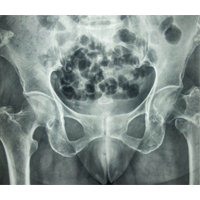

Case:10 Pathological Fracture

Seconderies from CA Prostate in 65 years old male patient treated with cemented bipolar prosthesis.

Pre-op

Post-op X-ray